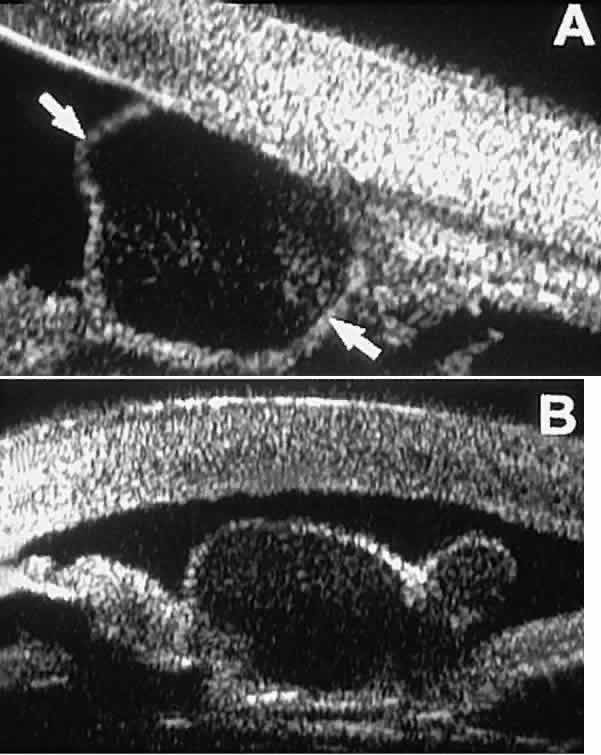

Postoperative UBM imaging of the anatomic changes caused by glaucoma surgery

often helps to explain mechanisms of success and failure of the

various surgical procedures (Fig. 12).3,4 After laser iridotomy, UBM can show whether the iridotomy is partial thickness (see Fig. 12A) or full thickness (see Fig. 12B) and whether the plane of curvature of the peripheral iris has changed

compared with the pretreatment findings. After trabeculectomy (see Fig. 12C), UBM can show whether the scleral aperture is patent or blocked internally, whether

the peripheral iridectomy is open or blocked, and whether

the filtering bleb is flat, shallow, or deep.9 After tube shunt surgery (see Fig. 12D), UBM can show the position of the tip of the tube and whether its orifice

is open or plugged.  Fig. 12. UBM features in glaucomatous eyes after treatment or filtering surgery. A. Incomplete peripheral iridectomy created by laser. B. Full-thickness peripheral iridectomy created by laser. C. Postoperative features of trabeculectomy including peripheral iridectomy, inner

scleral defect, thin residual scleral flap, and overlying conjunctival

filtering bleb. D. Tube shunt projecting radially into anterior chamber; note that the tube “shadows” deeper structures. Fig. 12. UBM features in glaucomatous eyes after treatment or filtering surgery. A. Incomplete peripheral iridectomy created by laser. B. Full-thickness peripheral iridectomy created by laser. C. Postoperative features of trabeculectomy including peripheral iridectomy, inner

scleral defect, thin residual scleral flap, and overlying conjunctival

filtering bleb. D. Tube shunt projecting radially into anterior chamber; note that the tube “shadows” deeper structures.

|

After any type of glaucoma filtering surgery,10 UBM can be used to detect and evaluate the extent of postoperative complications

such as ciliochoroidal effusion and cyclodialysis.3,4 In ciliochoroidal effusion (Fig. 13A), UBM shows the ciliary body to be edematous and separated from the sclera

by a sonolucent collection of supraciliary fluid. Many ciliochoroidal

effusions that are too limited in extent to be detectable by indirect

ophthalmoscopy and slit lamp biomicroscopy can be imaged by UBM. In

cyclodialysis (see Fig. 13B), UBM shows a well-defined separation between the uveal tissue and the

sclera in the region of the scleral spur. The width of the cleft is usually

assessed best by means of limbus-concentric images through the

region of interest.  Fig. 13. Complications of intraocular surgery. A. Postoperative ciliochoroidal effusion appears as slitlike spaces filled

with serous fluid posterior to scleral spur. B. Postoperative cyclodialysis appears as complete separation of iris and

ciliary body from sclera in region of scleral spur. Fig. 13. Complications of intraocular surgery. A. Postoperative ciliochoroidal effusion appears as slitlike spaces filled

with serous fluid posterior to scleral spur. B. Postoperative cyclodialysis appears as complete separation of iris and

ciliary body from sclera in region of scleral spur.